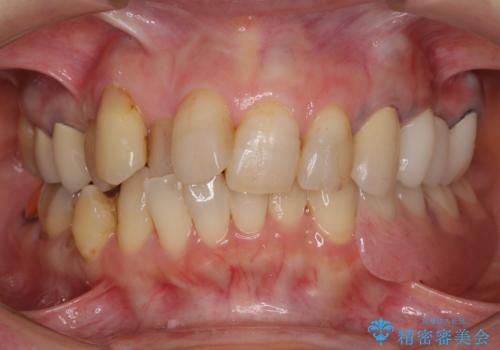

ノンクラスプデンチャー(金属止め具のない入れ歯)で左側の咬合回復

- 奥歯が痛いことを主訴にご来院された患者様です。入院してしまい、治療を2年間放置してしまったとのことでした。

左上は、抜歯とブリッジ治療を行いました(抜歯前に医師と対診)。

左下は、現在も抗がん治療を続けているため、観血的処置(インプラントなどの外科)はなるべく避けたいとのことで入れ歯を希望されました。それに伴い、入れ歯を支える歯のクラウンやりかえも行いました。

患者様はインプラント等の外科処置は希望されなかったため、セラミックと義歯で治療を行いました。

義歯を製作する際は、支えとなる歯の治療も同時に行うことで、義歯の製作が容易になります。

今回もそのように製作したところ、適合がよく安定のよい義歯になりました。患者様本人も使っていて全く痛くないとのことで、追加の調整もなく使用して頂いてます。患者様には、大変満足して頂きました。